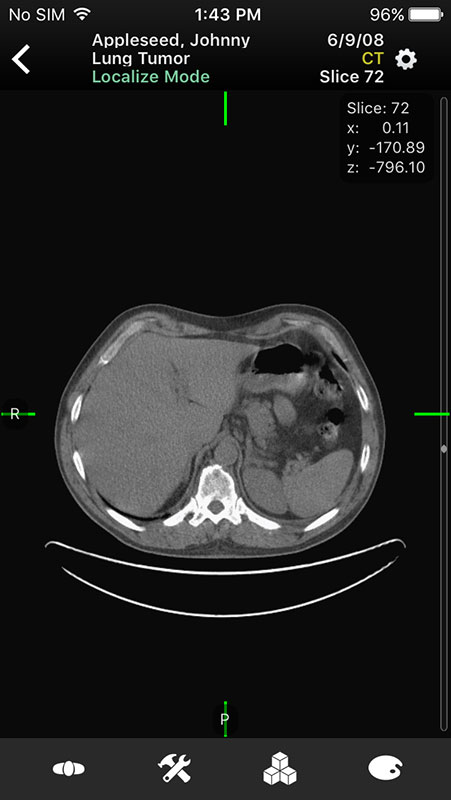

Just like in Mobile MIM app, images open in multi-planar view allowing users to choose series depending on the type of imaging technique, add annotation, or measure the image.

For example, flicking screen right or left enables users to switch between series, planes, and images, while swiping up and down switches between planes, or images in the series (with 2D images).

Users can also scroll through slices by using the scroll area on the right edge of the screen. However, it's invisible and it can easily trigger another (unwanted) action.